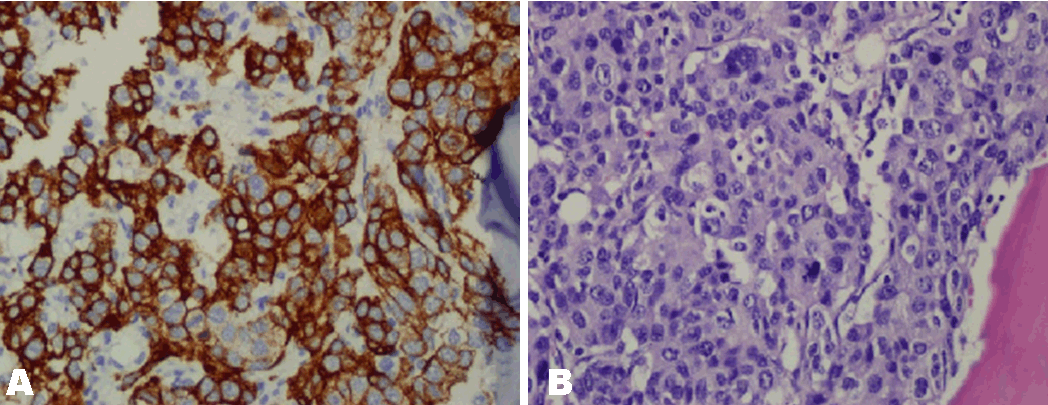

On admission, laboratory results showed anemia, thrombocytopenia and schistocytes in peripheral blood smear. The patient was transfused five units of packed red blood cells and four units of platelet-rich plasma. Clotting tests revealed elevated D-dimer 1170 µg/mL; normal value <250 µg/mL, normal level of fibrinogen (210 mg/dL; normal value >200 mg/dL) and a low platelet count 6.0x103/µL; normal value 150–400x103/µL), a slightly higher level of INR, low haptoglobin levels, elevated serum LDH and indirect bilirubin levels which led us a diagnosis of cancer related thrombotic microangiopathy (CR-TMA). His electrolyte panel was normal with a BUN 12 and a creatinine 0.8. The remainder of his chemical profile was normal. Despite receiving intensive therapy for CR-TMA, his clinical status worsened. Bone marrow biopsy led to a diagnosis of disseminated carcinomatosis of the bone marrow caused by AGC (Figure 2). Thrombocytopenia of uncertain origin with slightly high INR, APTT, elevated D-dimer, normal fibrinogen, proofs of intravascular hemolysis and schistocytes in peripheral blood smear led us the diagnosis of TMA. We initiated combination chemotherapy with 5-flourouracil (5-FU) and cisplatin (CIS), which led to a significant improvement of the CR-TMA. Now he is completing the 5th cycle of a planned six cycles of his treatment.

Figure 2: Bone marrow biopsy showing (A) Pan CK7 positivity (magnification: x40), (B) Abundance of signet ring cells (magnification: x40).